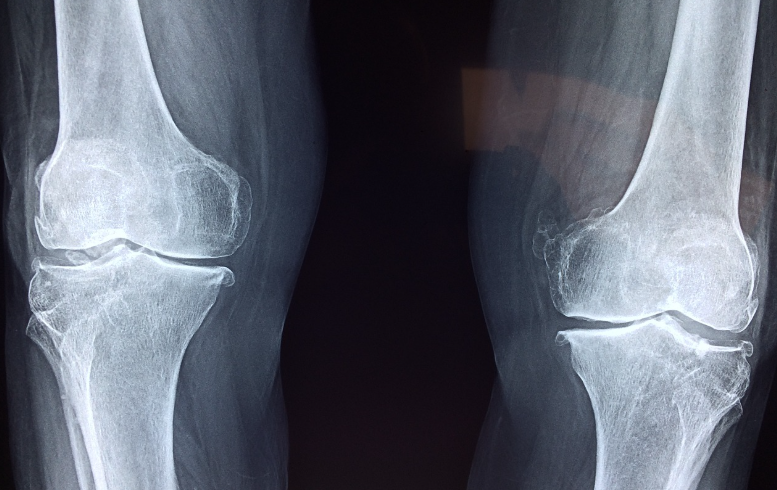

MSM이 관절에 좋은 이유

1. 항염증 작용

MSM은 항염증 작용을 통해 관절 통증 완화에 도움을 줍니다. 특히 염증을 유발하는 사이토카인의 생성을 억제하여 염증 반응을 줄여줍니다. 이는 관절염으로 인한 통증 완화에 매우 효과적입니다.

2. 콜라겐 합성 촉진

MSM은 콜라겐 합성을 촉진하여 관절 연골의 탄력성과 강도를 높여줍니다. 관절 연골은 나이가 들수록 손상되고 얇아지기 쉬운데, MSM을 섭취하면 연골이 손상되지 않도록 보호하고 재생을 도와줍니다.